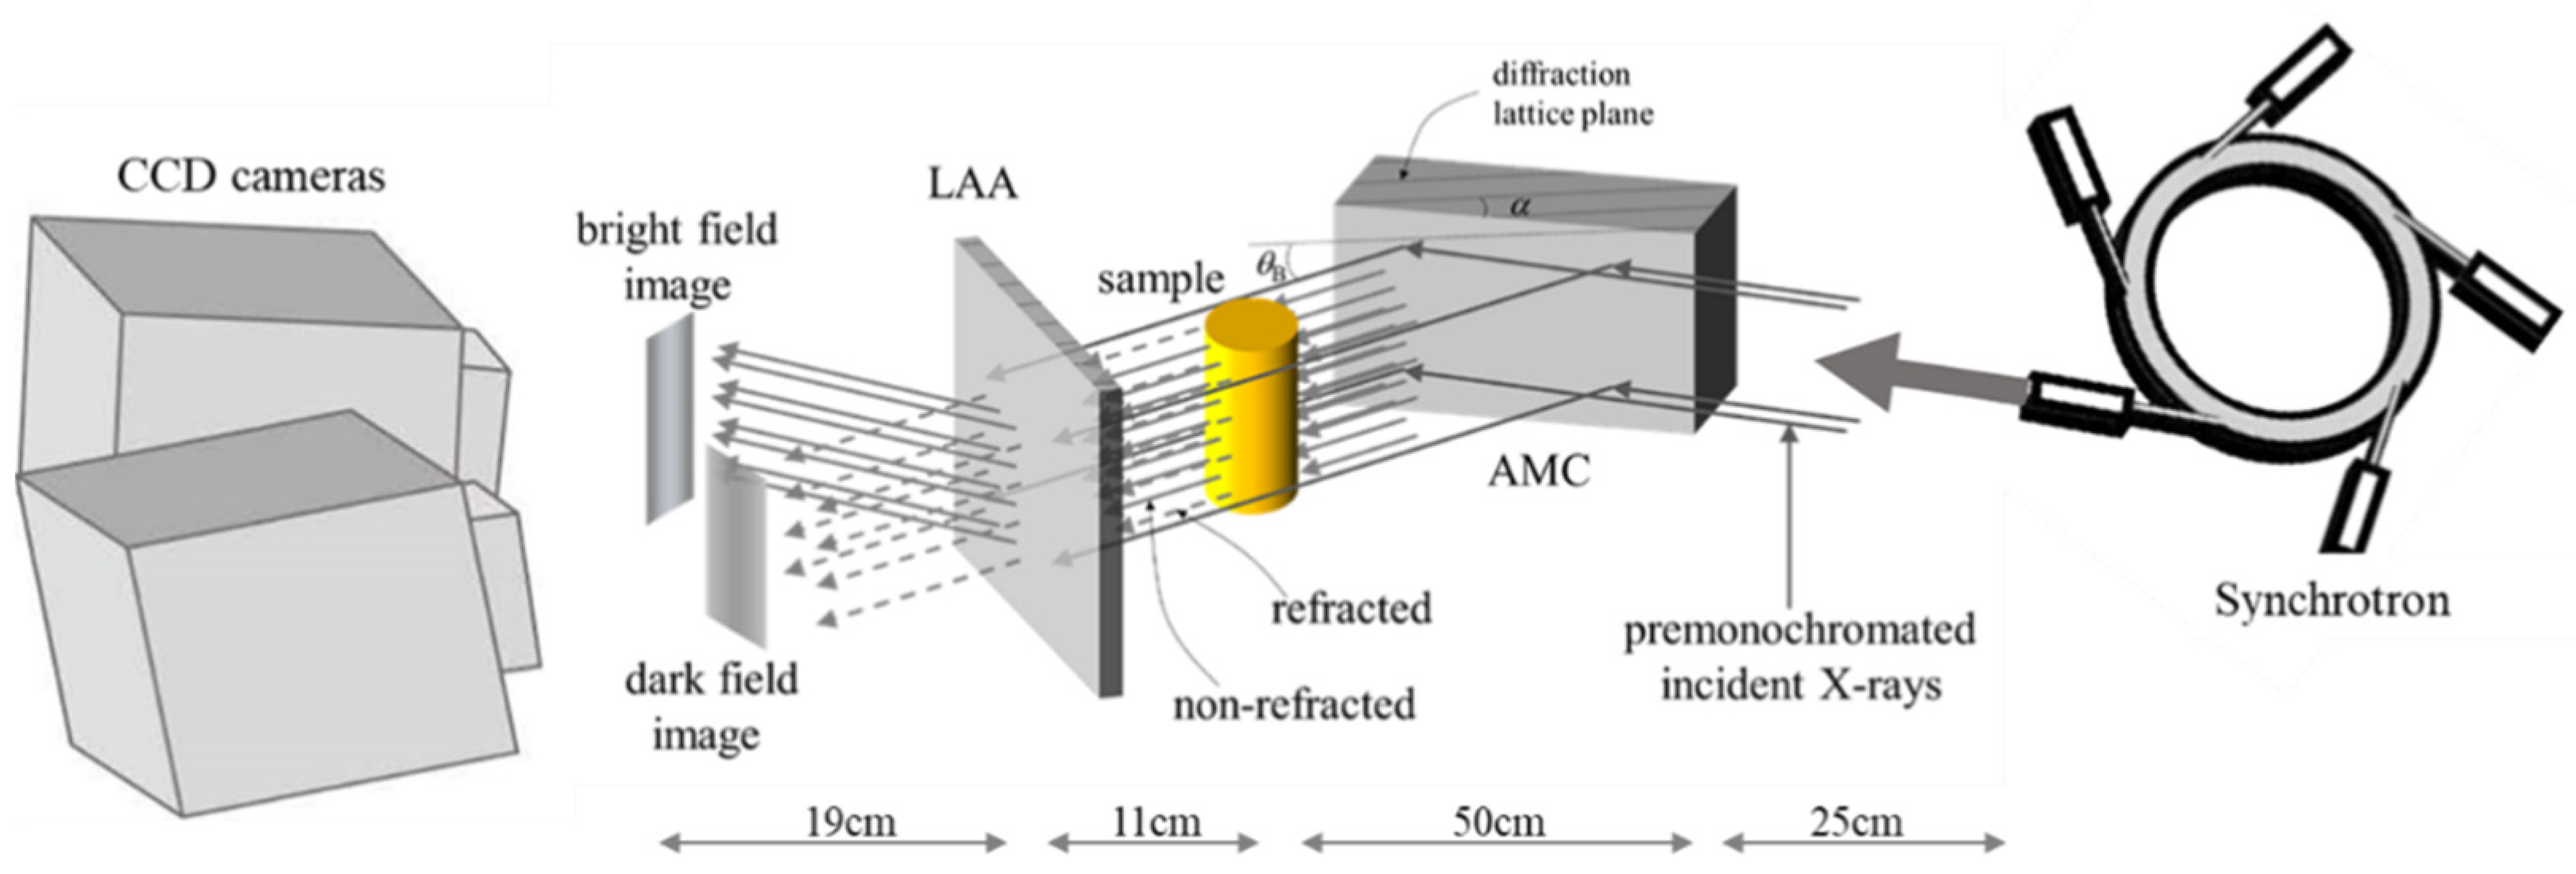

2.2. X-ray Source and Experimental Setup

2.3. Acquisition and Comprehension of Imaging Data